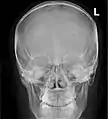

Paranasal sinuses seen in a frontal view